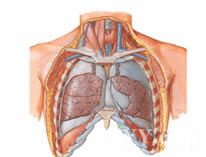

2.臨床表現 分兩部分,一是原發病表現;一為乳糜胸本身症狀。創傷性胸導管破裂,乳糜液溢出迅速,可產生壓迫症狀,如氣促呼吸困難、縱隔移位等。由疾病引起者少有症狀。可因脂肪蛋白、電解質丟失過多而營養不良,或因T淋巴細胞丟失過多而出現免疫功能缺陷。